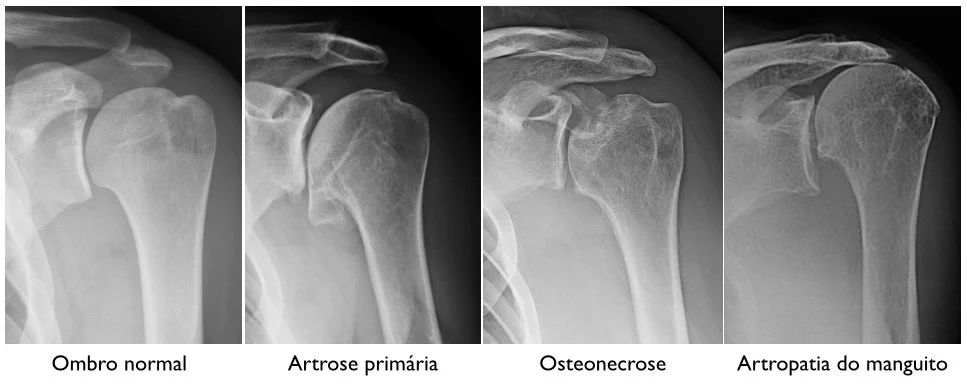

Graus de Artrose (Kellgren–Lawrence)

- Grau 1: Sinais discretos

- Grau 2: Estreitamento leve

- Grau 3: Desgaste moderado

- Grau 4: “Osso com osso” (desgaste avançado)

Diagnóstico da Artrose

O diagnóstico é feito por exame físico e radiografia. Em alguns casos, ultrassom e ressonância ajudam a avaliar estruturas adicionais, como derrame articular e tendões inflamados.